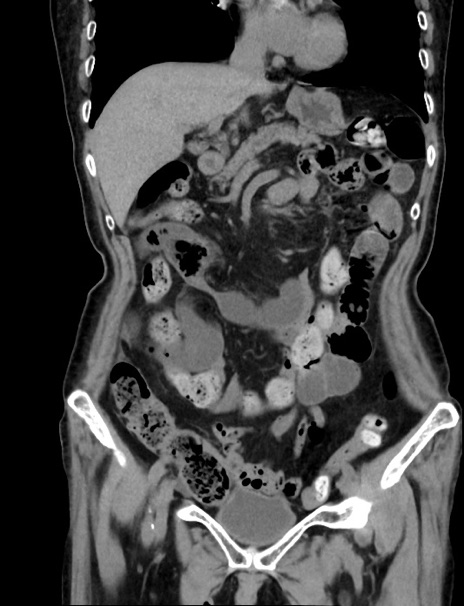

症例33(冠状断像)

【症例】70歳代 女性

【主訴】心窩部痛

【現病歴】延髄病変の精査・加療にて神経内科入院中。本日より心窩部痛あり。

【身体所見】右下腹部を中心に圧痛と反跳痛あり。

【データ】WBC 10900、CRP 0.02